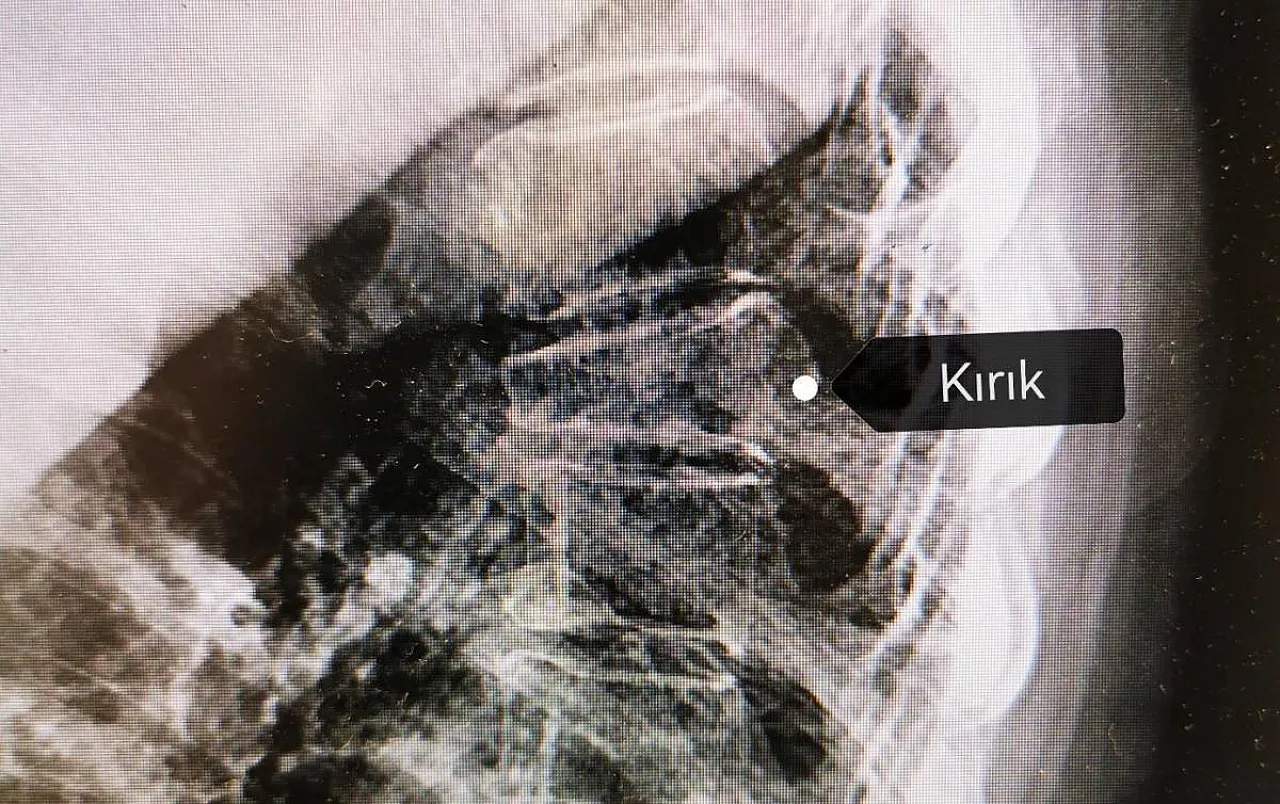

Afyonkarahisar Sağlık Bilimleri Üniversitesi Sağlık Uygulama ve Araştırma Merkezi Fizik Tedavi ve Rehabilitasyon Ana Bilim Dalı’ndan Prof. Dr. Hasan Toktaş, kemik erimesi (osteoporoz) hakkında ayrıntılı bilgi verdi. Toktaş, “Osteoporoz yani kemik erimesi, “gözenekli kemik” anlamına gelmektedir. Kırıklara yatkınlık ile birlikte düşük kemik mineral yoğunluğu (BMD) ile ilgili bu rahatsızlık, kemiğin iç yapısındaki değişikliklerden kaynaklanır. Kemik erimesi; kırıklara, sakatlıklara, yaşam kalitesinin azalmasına neden olan; kemiğin içini boşaltıp kalitesini bozduğu için kırık olana kadar bulgu vermediğinden “sessiz hırsız” olarak da adlandırılan bir hastalıktır. Osteoporoza bağlı kırıklar genellikle kalçada, bileklerde ve omurgada görülür. Kalça kırıkları genellikle ameliyat gerektirir. Bilek kırıkları ise alçı ile tedavi mümkün olmazsa ameliyat gerektirebilir. Omurga, bilek ve kalça kırıkları, yaşlılarda en sık görülen kırıklardır. Kemiklerin zayıflaması, omurgayı oluşturan kemiklerden her biri olan omurlarda kompresyon (çökme) kırıklarına yol açabilir. Kompresyon kırıklarının zamanla omurganın gücünü ve şeklini değiştirmesi kronik sırt ağrısına veya kamburluğa sebep olabilir, boy kısalabilir” dedi.

“Bel bölgesi omurgada, kalça eklemi bölgesinde veya ön kolun bilek bölgesinde kemik yoğunluğu ölçümü ile tanısı konur. Kemik dansitometresi ölçümünde T -skoru -2,5 veya daha düşük bulunması ile teşhis edilir. Erkeklerde ve menopoz öncesi kadınlarda Z skoruna bakılır ve muayene, laboratuvar ve röntgen bulgularına göre tanı konur. Çocuklarda tüm vücut kemik dansitometresi Z skoruna bakılır. Ek olarak Kemik dansitometresinde T skoru osteoporoz sınırından daha yüksekte olan hastalarda risk faktörleri mevcutsa osteoporoz tanısı konur. Kadınlarda, menopozdan sonraki ilk beş ila yedi yıl içinde kemik kaybı hızlıdır. Özellikle 40 yaşından önce yumurtalıkların alınması veya başka bir sebeple erken menopoza giren kadınlar, risk altındadır. Zayıf veya minyon tipli kadınlar, sigara içenler, alkol tüketenler, hareketsiz bir yaşam tarzı sürdürenler, ailesinde kalça kırığı öyküsü olanlar, hormonal bozukluğu olanlar, kemik metabolizma hastalığı olanlar, tiroit hastalığı olanlar, diyabeti olanlar, kronik böbrek yetmezliği olan hastalar ve kronik karaciğer hastaları, risk altındadır. Felç veya hastalık nedeniyle uzun süreli hareketsizlik de kemik kaybına neden olabilir.”